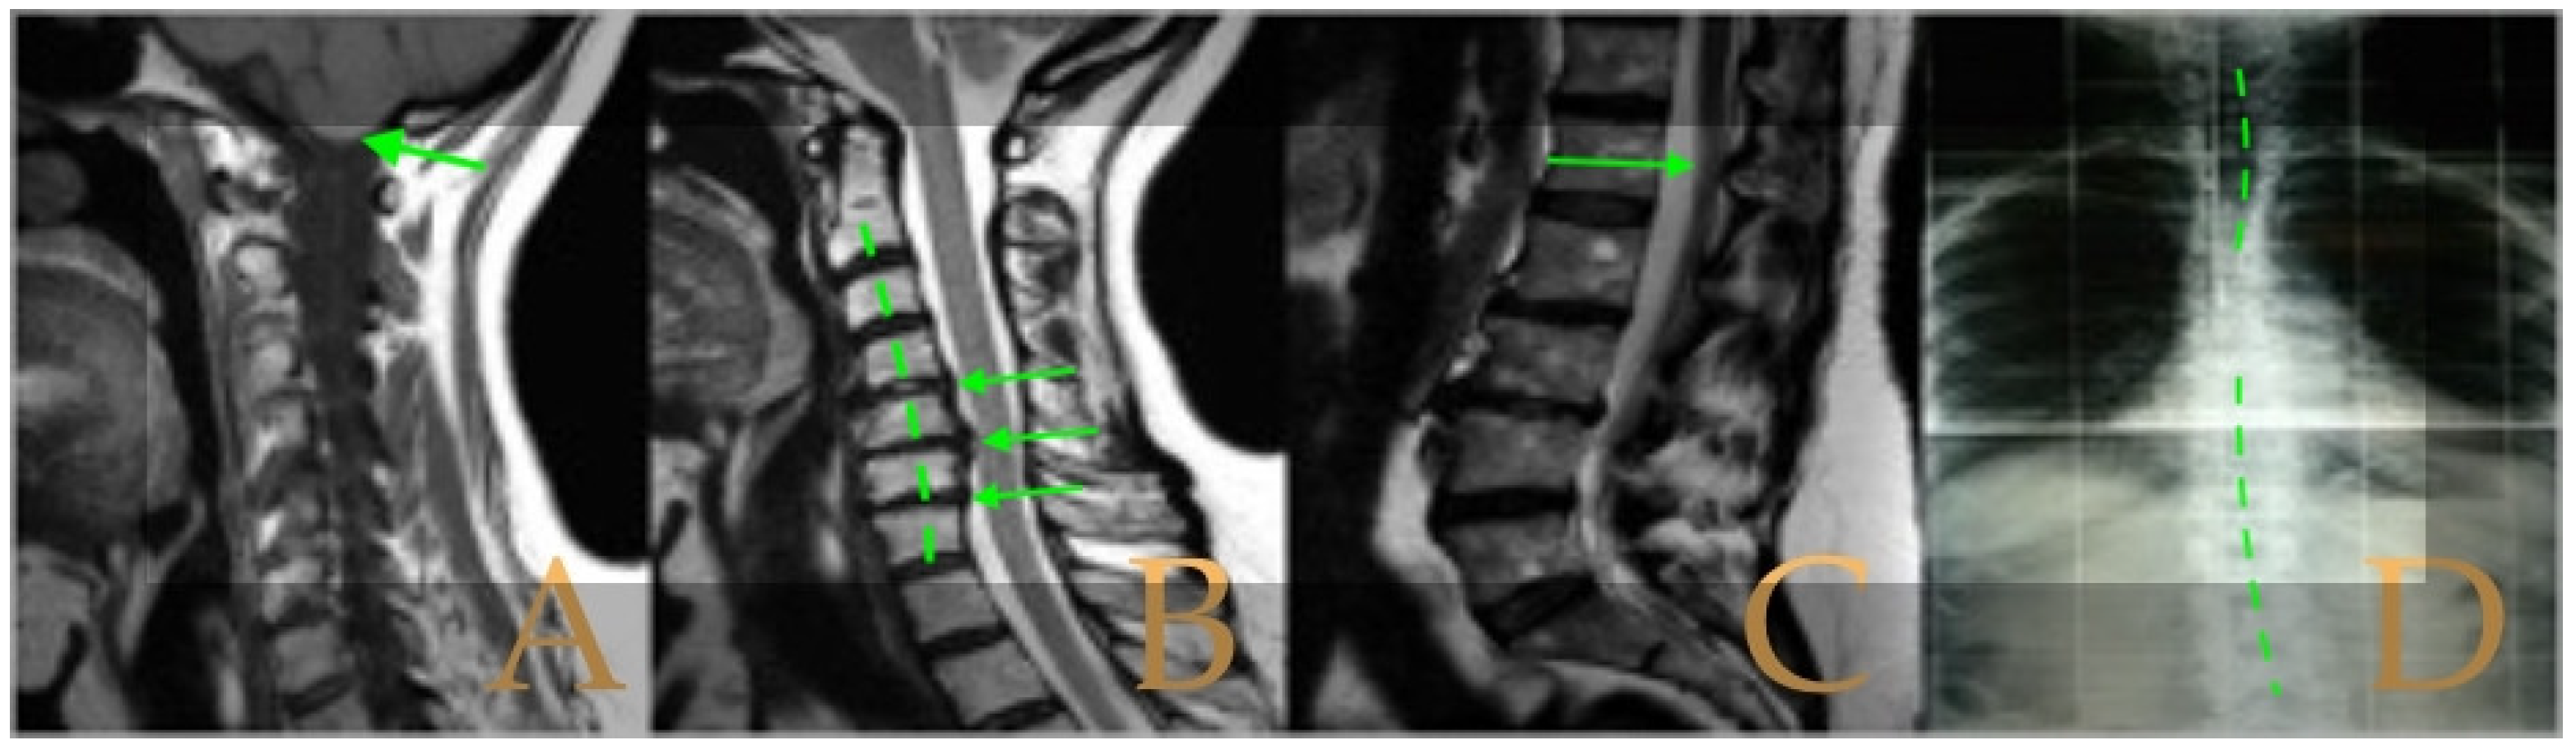

Magnetic resonance imaging showed a slight descent of the cerebellar tonsils, multiple diseased discs, and conus medullaris at the level of the middle third of the L1 vertebra. The X-ray images of the entire spine revealed a mild dextroconvex thoraco-lumbar scoliosis with 5° Cobb angle (Figure 1).

Figure 1.

Imaging of patient 1. A: Mild descent of the cerebellar tonsils (arrows); B: multiple disc disease (arrows) and straightening of the cervical spine (interrupted line); C: conus medullaris at the middle third of L1 (arrow); and D: mild deviation of the vertebral column (interrupted lines).